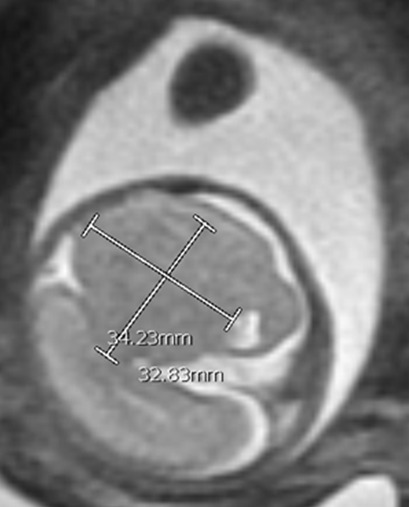

A 24-year-old gravida 1 with a dichorionic-diamniotic twin pregnancy at 16w1d gestation was evaluated by Maternal-Fetal Medicine who identified multiple possible cranio-facial abnormalities in Twin A on transabdominal ultrasound. This raised the concern for a possible chromosomal abnormality as well as holoprosencephaly as the cavum septum pellucidum was not visualized. A detailed transabdominal ultrasound performed at 16w1d provided the initial assessment of the abnormal-appearing left cerebrum of Twin A (Figure 1). The left cerebral ventricle was overall poorly visualized, however, the posterior aspect of the left ventricle appeared to be significantly more dilated compared to the normal-appearing right ventricle. The cavum septum pellucidum could not be visualized, the thalami appeared fused, and the temporal areas of the facies appeared more angulated than expected. The patient was scheduled for a fetal MRI which was performed at 19w1d gestation and showed complete architectural distortion involving the left cerebral hemisphere of Twin A, with a mass-like structure measuring approximately 2.4 x 2.3 x 1.8 cm, along with a loss of normal gray-white differentiation (Figure 2). The diagnoses based on this MRI were either a neoplastic growth or a migrational anomaly.

At 23w0d a limited fetal MRI was repeated (Figure 4). This study demonstrated, again, the supratentorial left hemispheric mass measuring 3.3 x 3.5 x 2.4 cm within the cerebrum of Twin A. Most notably, there was an interval increase in the size of the mass relative to the skull diameter, as well as a prominent mass effect on the contralateral hemisphere with an associated midline shift. This second fetal MRI finding was interpreted as most consistent with an enlarging intracranial neoplasm with the differential diagnoses including astrocytoma, intracranial teratoma, and glioblastoma multiforme; however, no distinctive features were noted to confirm one of these diagnoses. The interval growth of the mass was interpreted as characteristic of an aggressive fetal neoplasm; therefore, a migrational anomaly was seen as less likely.